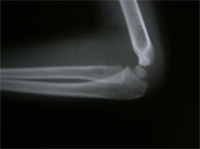

The Monteigga Injury

The Monteigga-fracture dislocation is an injury complex where there is fracture of the ulna and dislocation of the radial head. The ulnar fracture may be incomplete or complete and sometimes there is only plastic deformation of the ulna bone. The injury assumes importance due to the frequency with which the radial head dislocation is missed. Acute injuries of the forearm should always be followed by thorough examination of the wrist and elbow.

Biplanar radiographs should include the wrist joint and elbow joint to rule out any joint subluxation or dislocation. Two cases of late presenting Monteigga Fracture — Dislocation. Clinical Features